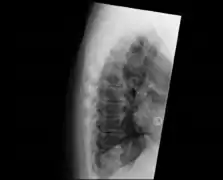

| DISH in an 80 year old female, also with T11 fracture. | |